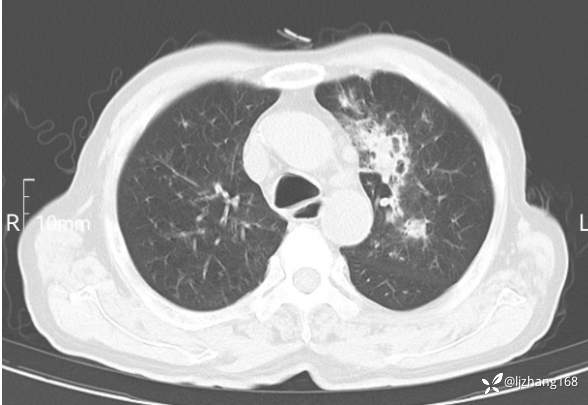

辅助检查:胸部CT:双肺肺气肿,间质性病变,血气分析:PH 7.413, PCO2 29.2mmHg, PO2,81.8mmHg,乳酸 3.3mmol/1,剩余碱-4.0mmol/1,HC03 18.8mmol/1。全血超敏C反应蛋白:超敏C反应蛋白 135.60 mg/L、 白细胞 14x19^9/L,中性粒细胞11.6x10^9/L。